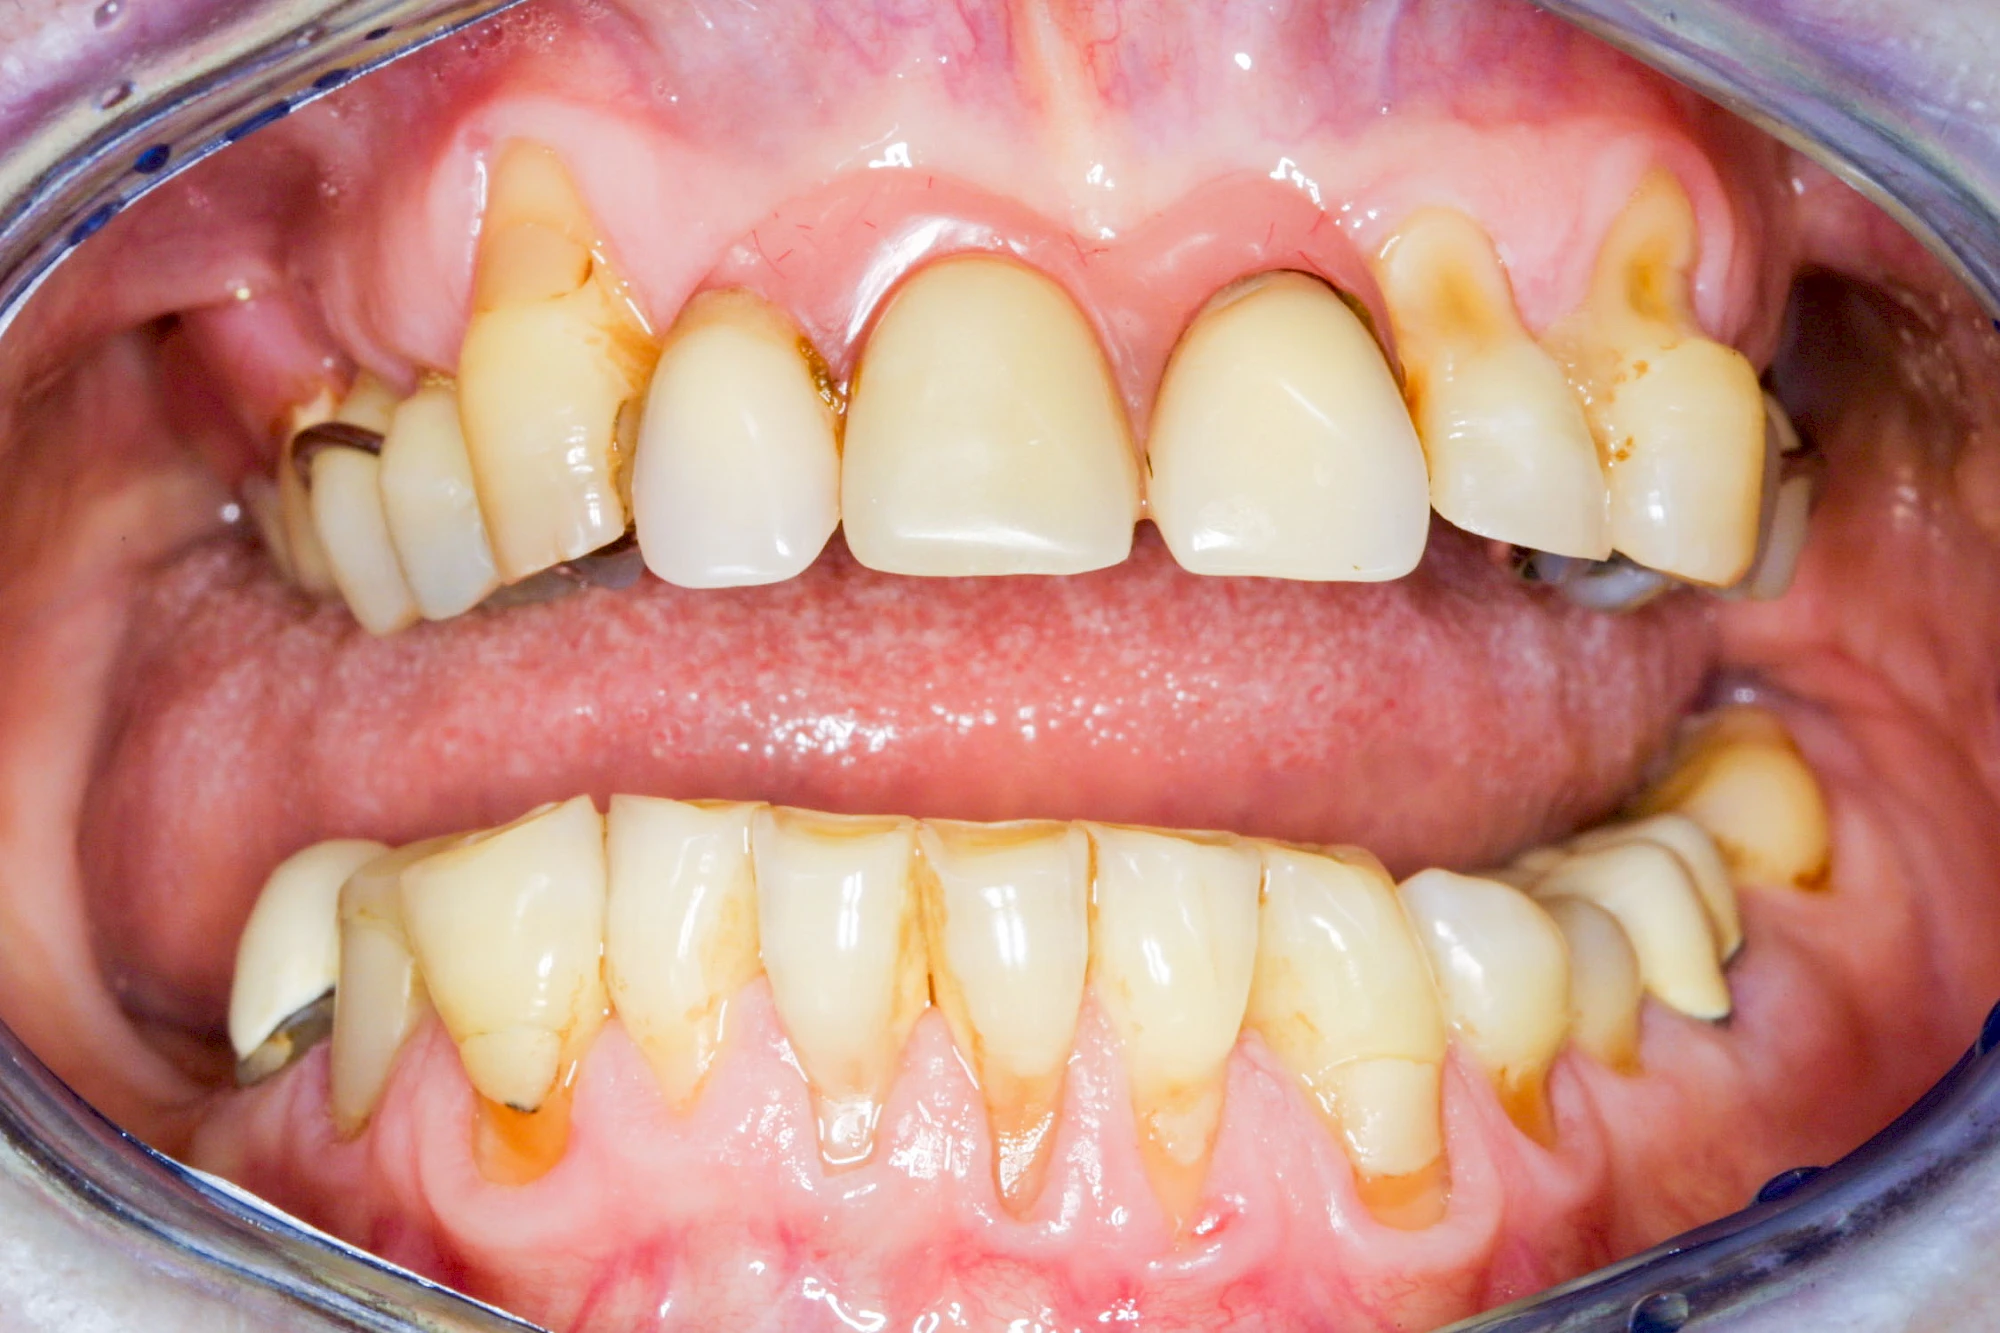

Bakterien in den Zahnbelägen greifen neben den Zähnen auch das Zahnfleisch (Gingiva) und den gesamten Zahnhalteapparat (Parodont) an. Der Körper reagiert mit einer Entzündung, sichtbar als Rötung und Schwellung. Meist blutet das Zahnfleisch z .B. beim Essen oder auch beim Putzen der Zähne.

Ist zunächst nur das Zahnfleisch von der Entzündung betroffen, spricht man von Gingivitis. Später, wenn auch der Knochen um die Zähne herum entzündet ist, spricht man von einer Parodontitis. Bei der Parodontitis wird der Knochen nach und nach abgebaut und das Zahnfleisch zieht sich zurück. Die Zahnhälse und Zahnwurzeloberflächen liegen mehr und mehr frei. Die Zähne werden zunehmend lockerer und fallen schließlich aus.